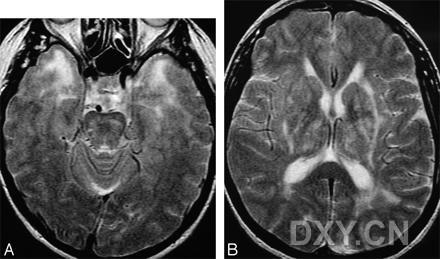

脑白质疏松,脑白质疏松CT

脑白质疏松( la ) : 小动脉病变导致的白质纤维脱髓鞘;t2-f

脑白质疏松图片

脑白质疏松ct图片

脑白质高信号